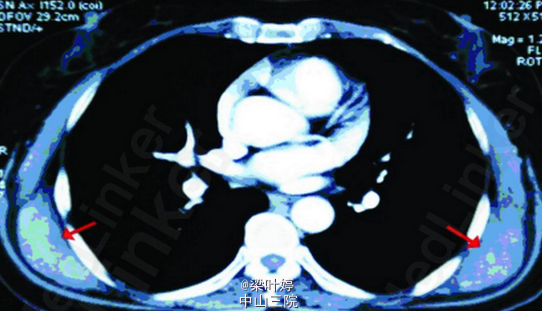

查体:双侧肩胛下角区域可扪及一直径约5cm 硬质类圆形包块,固定。余无特殊。 CT提示:双侧背阔肌及前锯肌深面对称性病变,增强后不均匀强化,周围脂肪间隙清楚。 MRI示::双侧对称性病变,位于背阔肌及前锯肌深面,增强后斑片状强化,周围脂肪间隙清晰,局部与肋骨骨膜关系紧密。